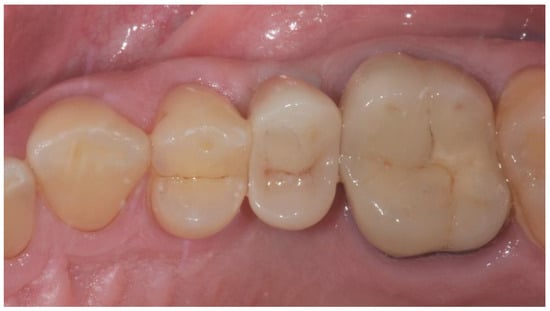

2.3. Prosthetic Protocol